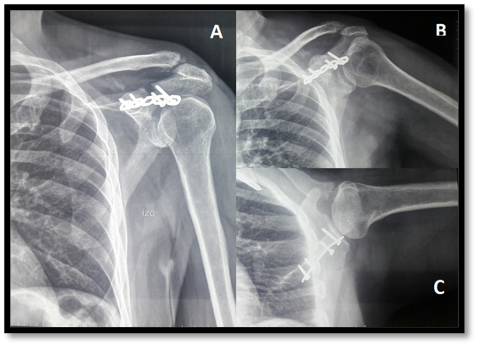

Una vez establecidos los diagnósticos se procedió bajo efectos de anestesia general, a realizar abordaje superior de hombro modificado. Divulsionado cuidadosamente respetando estructuras nobles, acompañado de maniobras de reducción se realizó fijación de la base del acromion a la espina del omóplato con una placa de reconstrucción anatómica y fijación de la articulación acromioclavicular con dos clavijas de kirschner (fig. 2).

Figura 2. Radiografías de control postquirúrgicas evidencian las presencia de placa de reconstrucción a nivel de acromion y Fijación con clavijas en articulación acromioclavicular satisfactoria. Proyección anteroposterior de hombro (A), Transtorácica(B), lateral (C).